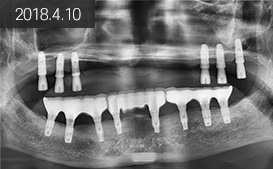

상악 : 6개 식립 후 고정식 임플란트 틀니 제작 /

하악 : 8개 식립 후 3유닛으로 보철 완성

“ 타원에서 위 임플란트를 포기.. 아래에 한 임플란트로는 씹기가... 힘들었어요 ”

초진 2010.8.3 (75세)

완성 2011.11.25

2014.7.16

2016.8.2

2018.4.10

2019.7.24

정기 체크